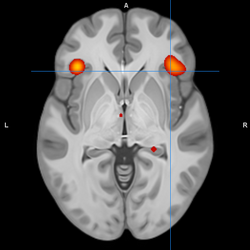

The main loci of neuroimaging and neuropathological findings in bipolar have been proposed to constitute dysfunction in a "visceromotor" network, composed of the medial prefrontal cortex (mPFC), anterior cingulate cortex (ACC), orbitofrontal cortex (OFC), hippocampus, amygdala, hypothalamus, striatum and thalamus.[32]

A model of functional neuroanatomy produced by a workgroup led by Stephen M. Strakowski concluded that bipolar was characterized by reduced connectivity, due to abnormal pruning or development, in the prefrontal-striatal-pallidal-thalamic-limbic network leading to dysregulated emotional responses. This model was supported by a number of common neuroimaging findings. Dysregulation of limbic structures is evinced by the fact that hyperactivity in the amygdala in response to facial stimuli has been consistently reported in mania.[33] While amygdala hyperactivity is not a uniform finding, a number of methodological challenges could explain discrepancies. As most studies utilize fMRI to measure blood-oxygen-level dependent signal, excess baseline activity could result in null findings due to subtraction analysis. Furthermore, heterogenous study design could mask consistent hyperactivity to specific stimuli. Regardless of directionality of amygdala abnormalities, as the amygdala plays a central role in emotional systems, these findings support dysfunctional emotional circuits in bipolar. A general reduction in ventrolateral prefrontal cortex activity is observed in bipolar, and is lateralized with regard to mood (i.e., left-depression, right-mania), and may underlie amygdala abnormalities. The dorsal ACC is commonly under-activated in bipolar, and is generally implicated in cognitive functions, while the ventral ACC is hyperactive and implicated in emotional functions. Combined, these abnormalities support the prefrontal-striatal-pallidial-thalamic limbic network underlying dysfunction in emotional regulation in bipolar disorder.[34] Strakowski, along with DelBello and Adler have put forward a model of "anterior limbic" dysfunction in bipolar disorder in a number of papers.[35][36][37][38][39]

During cognitive or emotional tasks, functional neuroimaging studies, consistently find hyperactivation of the basal ganglia, amygdala, and thalamus. Prefrontal abnormalities are less consistently reported, although hyperactivation in the ventral prefrontal cortex is a fairly consistent finding.[72] Hyperactivity in the amygdala and hypoactivity in the medial and ventral prefrontal cortex during exposure to emotional stimuli has been interpreted as reflecting dysfunction in emotional regulation circuits. Increased effective connectivity between the amygdala and orbitofrontal cortex, and elevated striatal responsiveness during reward tasks have been interpreted as hyper-responsiveness in positive emotion and reward circuitry. The abnormal activity in these circuits has been observed in non-emotional tasks, and is congruent with changes in grey and white matter in these circuits.[73] Neural response during reward tasks differentiates unipolar depression from bipolar depression, with the former being associated with reduced neural response and the latter being associated with elevated neural response.[74] An ALE meta analysis of functional neuroimaging comparing adults and adolescents found a larger degree of hyperactivity in the inferior frontal gyrus and precuneus, as well as a larger degree of hypoactivity in the anterior cingulate cortex in adolescents relative to adults[75]